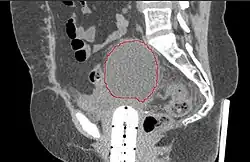

- Postoperative Lymphocele

-